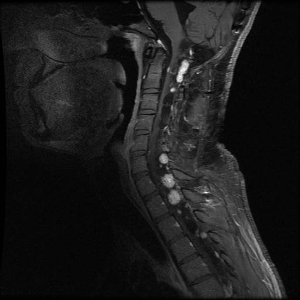

Los hemangioblastomas son la manifestación más común en los pacientes con enfermedad de VHL y afectan a más del 70 % de las personas. En un estudio prospectivo se evaluó la evolución natural del los hemangioblastomas.[16] La media de edad de aparición de los hemangioblastomas del sistema nervioso central (SNC) es de 29,1 años (intervalo, 7–73 años).[17] Los hemangioblastomas del SNC se observaron con mayor frecuencia en el cerebelo (45 %), la médula espinal (36 %), la cola de caballo (11 %) y el tronco encefálico (7 %).[18] Aunque los hemangioblastomas esporádicos son casi siempre solitarios por naturaleza, las lesiones en el SNC asociadas a la enfermedad de VHL a menudo son multifocales. Luego de una media de seguimiento de 7 años, el 72 % de 225 pacientes estudiados presentaron lesiones nuevas.[18] En las figuras 2 y 3 se muestran hemangioblastomas de cerebelo y médula espinal, respectivamente, en pacientes con enfermedad de VHL.